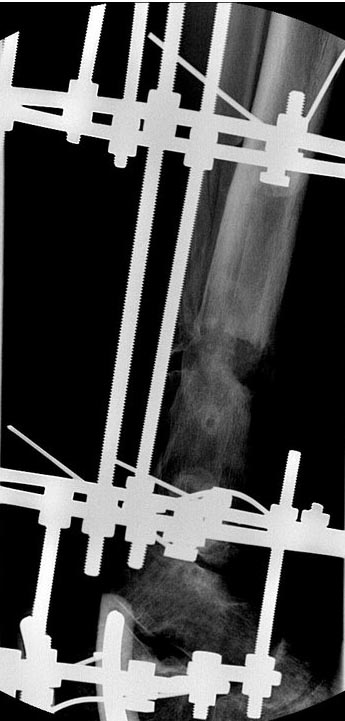

Уважаемые коллеги выразите Ваше мнение по следующему случаю.Молодой человек, 27 лет, находится на лечении с диагнозом: Ложный сустав большеберцовой кости в нижней трети, фиксированный интрамедуллярным блокированным стержнем (12.02.2014 г), ложный сустав малоберцовой кости в нижней трети левой голени, посттравматический артроз левого голеностопного сустава 1 стадии. Укорочение левой нижней конечности на 1,0 см. Со слов пациента известно, что в детстве получил перелом большеберцовой кости, лечился консервативно, перелом сросся с деформацией. Травма в июле 2010 г. бытовая-упал на лестнице, получил перелом малоберцовой кости, и перелом большеберцовой кости без смещения. Выполнена операция: Остеотомия большеберцовой кости в нижней трети, интрамедуллярный блокированный остеосинтез большеберцовой кости левой голени. Гладкое течение послеоперационного периода. Перелом большеберцовой кости сросся. Функция конечности восстановилась. В июне 2013 г выполнена операция удаление интрамедуллярного стержня из большеберцовой кости левой голени. Гладкое течение послеоперационного периода. Приступил к занятием физкультурой, бег. В августе 2013 г спрыгнул с автобуса, с чемоданом в руках, появилась резкая боль в левой голени. За медицинской помощью обратился через 7 дней, при обследовании выявлено: Рефрактура большеберцовой кости. Рекомендовано консервативное лечение в гипсовой повязке. В январе 2014 г. установлен диагноз: Ложный сустав большеберцовой кости в нижней трети, малоберцовой кости в нижней трети левой голени. Контрактура сгибательно - разгибательная левого голеностопного сустава. Посттравматический артроз левого голеностопного сустава 1 стадии. Укорочение левой нижней конечности на 1,0 см. В феврале 2014 г выполнил первым этапом: Фиксацию ложного сустава в АНФ с восстановлением осей сегментов. Через семь дней БИОС с рассверливанием. После операции - вальгус голеностопного сустава. Гладкое течение послеоперационного периода. Нагрузка по переносимости боли. Через 6 недель динамизация, через 2 недели стали мигрировать 2 фронтальных винта. Пытался подкрутить, пришлось удалить. Через 6 мес., контроль - линия ложного сустава прослеживается, но имеется периостальная костная мозоль. Не хватает стабильности.Вопрос что делать?Вариант № 1- выполнить реостеосинтез с рассверливанием КМК и на 12 мм диаметра гвоздь (стоит 11 мм)и убрать ротацию стопы руками одномоментно или одномоментно при помощи АНФ во время операции. Вариант № 2 выполнить удаление гвоздя, сделать все то же, что 6 месяцев назад, но с восстановлением анатомических взаимоотношений в голеностопном суставе.Вариант № 3 Двухэтапно, вторым этапом пластина на большеберцовую кость + костная пластика области не сращения.Вариант № 4 удаление гвоздя и лечение в КДА. Вопросы:1. Какой вариант оперативного лечения будет оптимальным в данном случае.2. При двухэтапной методике в дистальном отломке имеется канал от гвоздя, как направить гвоздь к наружному отделу дистального отломка большеберцовой кости. Есть опасения, что гвоздик может пойти по тому же каналу. Использовать поллер спицы или винты – сработают ли? И достаточна ли будет жесткость фиксации дистального отломка большеберцовой кости на гвоздике при 3 – 4 винтах при реостеосинтезе гвоздем.3. Нужен ли остеосинтез малоберцовой кости в нижней трети, с целью создания латеральной опоры. К сообществу за советом.

Здесь можно использовать все названные варианты. Гвоздь вполне тоже можно. Надо аппаратом восстановить длину и не повторять прежней ошибки - надо латеральную стенку сопоставить, а не оставлять наружного смещения. Да, надо ввести передне-задние спицы, чтобы не дать стержню попасть в старый канал. И длинной ручной разверткой лучше бы сформировать новый канал.

Можно сделать поперечную остеотомию периферического отломка на уровне конца центрального, и сместить его (периферический) кнутри.